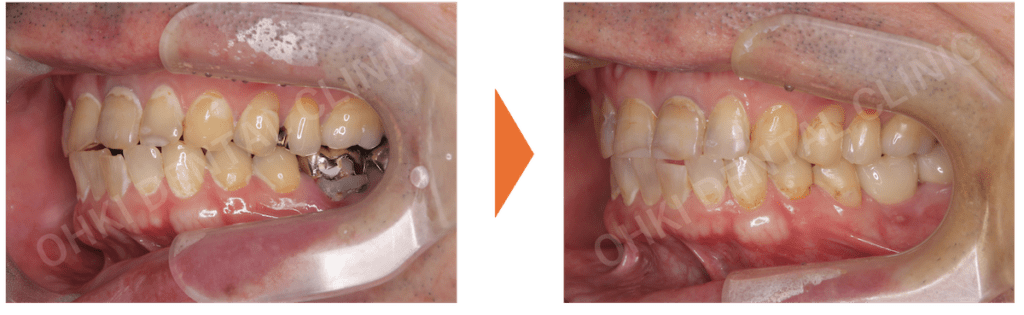

・主訴である右下7番は、コアごと脱離しており、歯根破折を認めました。

・パノラマレントゲン写真では、左下6番にも歯折と周辺の骨吸収が認められました。

現状の口腔内や今後の治療計画、費用について相談した上で、全身の健康状態も確認し、抜歯後は、骨・軟組織の治癒を待って、インプラント治療を行いました。今回は2本のインプラントを埋入しました。選択の理由は以下の3つです。

GBR(骨再生誘導法)を含めたインプラント埋入処置を実施しました。 - 上部構造の装着(ファイナルセット):

インプラント体に最終的なセラミック素材の上部構造をセットしました。

- インプラントを埋入したことにより、噛む機能が回復したことが大きな結果です。

- 噛み合わせの柱が再建されたことで、今後、残存している歯の破折リスクや負担が軽減されました。

- 歯が抜けたままの状態ではなく、天然歯に似た形態でセラミック素材の上部構造を作製したため、見た目(審美面)も改善し、歯が再生したような状態を実現できました。